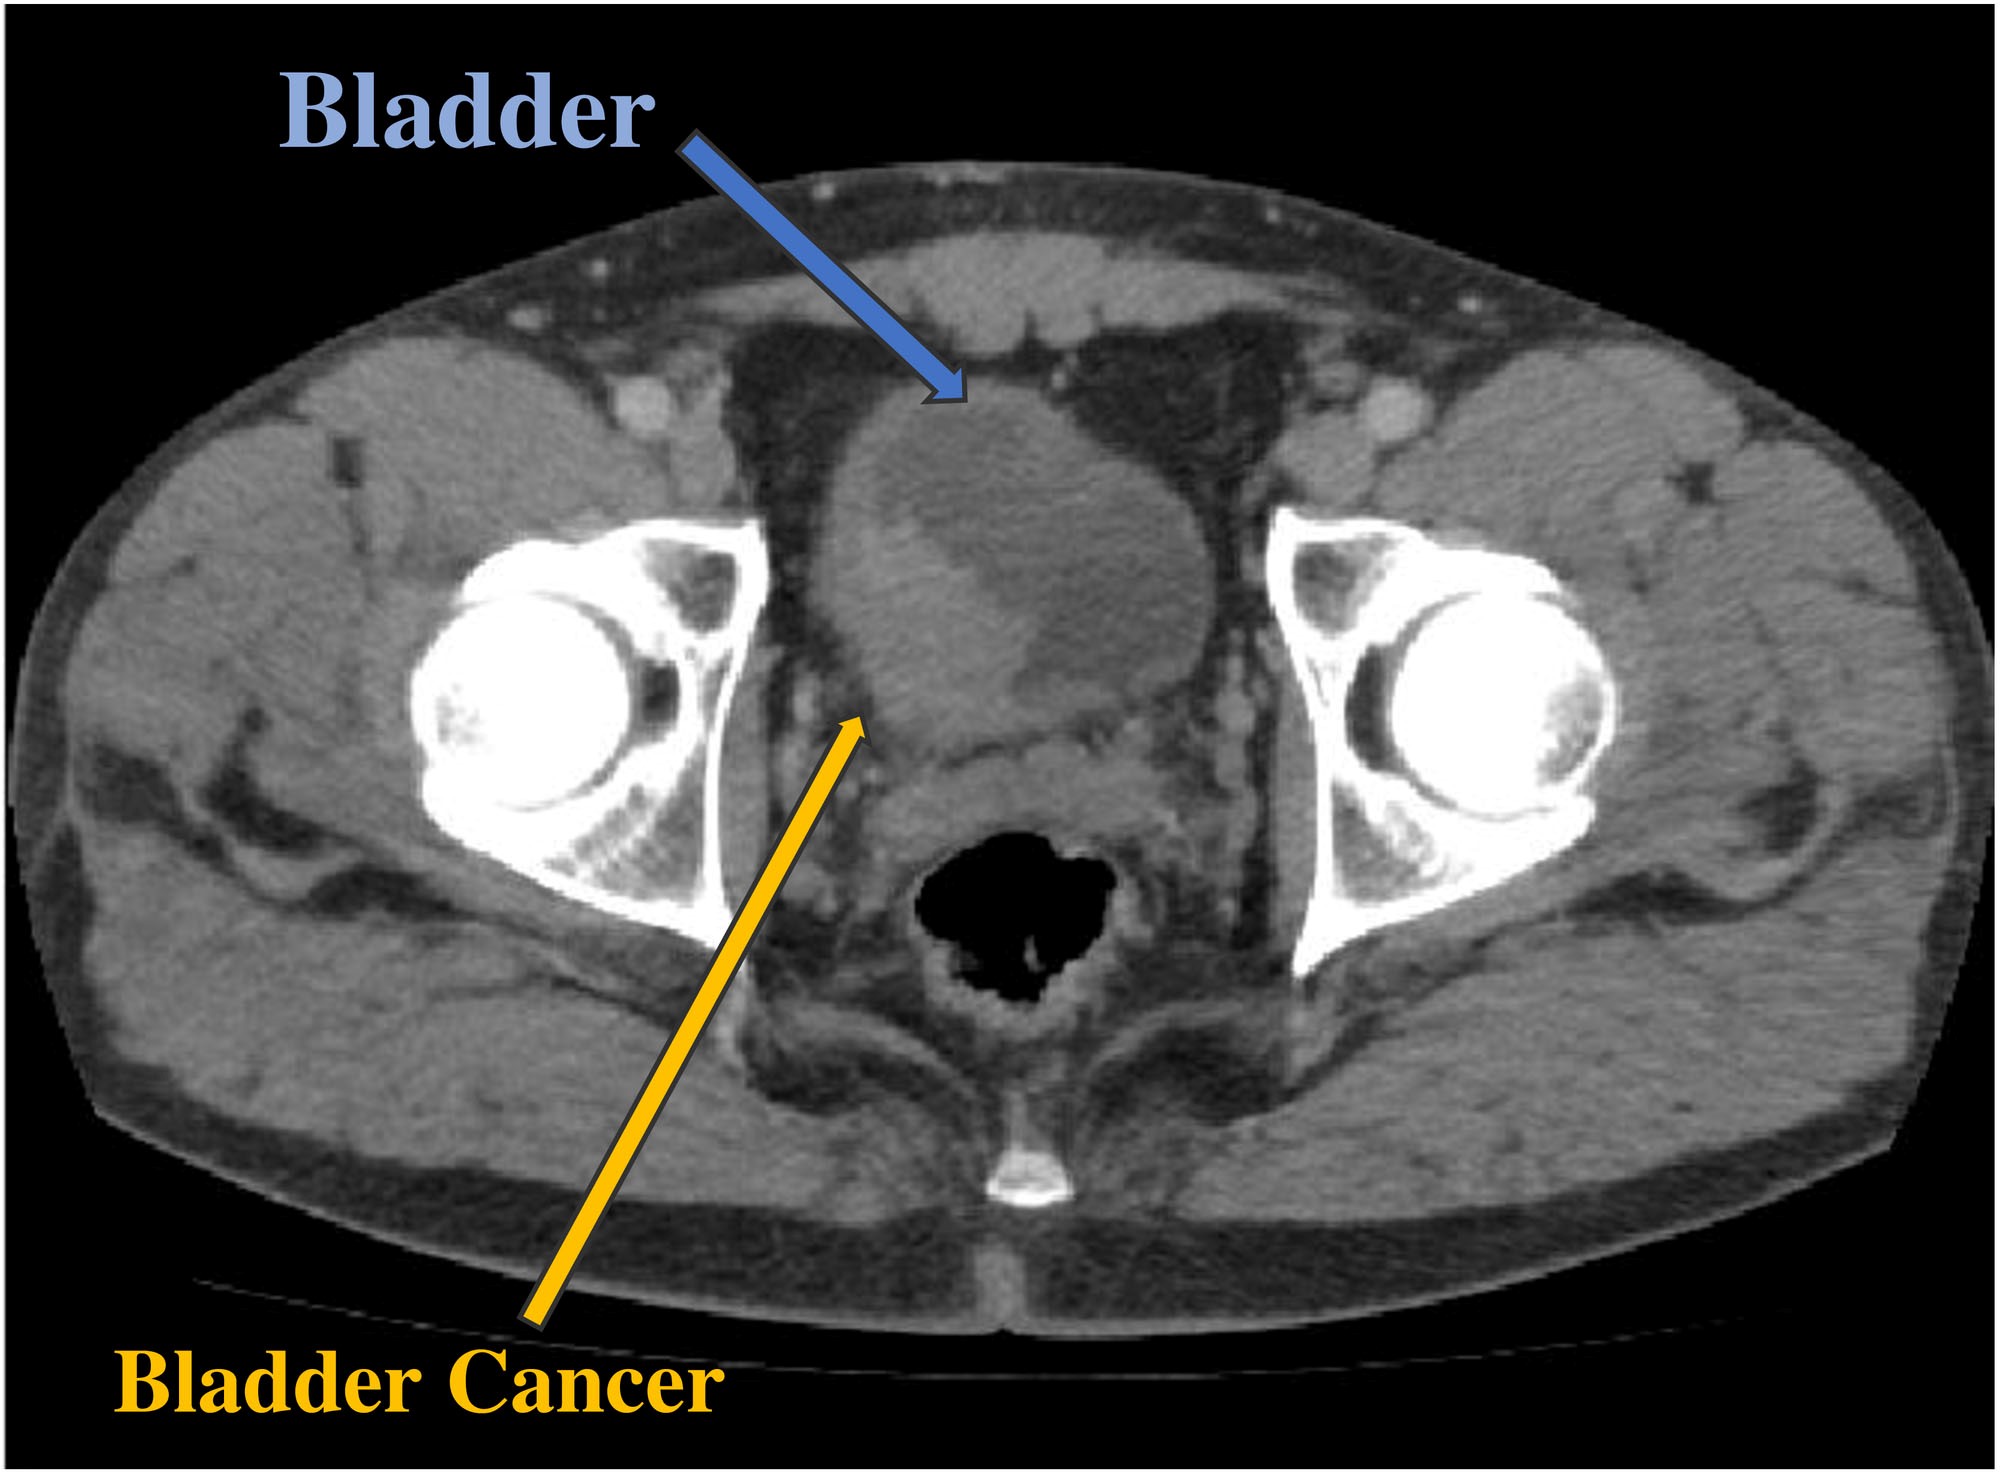

Imaging Techniques To Detect Bladder Cancer

Imaging techniques, which include ultrasound, computed tomography (or CT) scanning, magnetic resonance imaging (or MRI) and x-ray approaches, provide an important means of assessing the urinary tract, including the kidneys, and play an important role in the detection, diagnosis, and monitoring of bladder cancer.

Detecting bladder cancer with CT scans

A CT scan uses x-rays to obtain cross-sectional images of the body. Compared to a general x-ray test, which directs a broad x-ray beam from a single angle, the CT scan uses a number of thin beams to produce a series of images from different angles.

Detecting Bladder Cancer With Ct Scans

A CT scan uses x-rays to obtain cross-sectional images of the body. Compared to a general x-ray test, which directs a broad x-ray beam from a single angle, the CT scan uses a number of thin beams to produce a series of images from different angles.